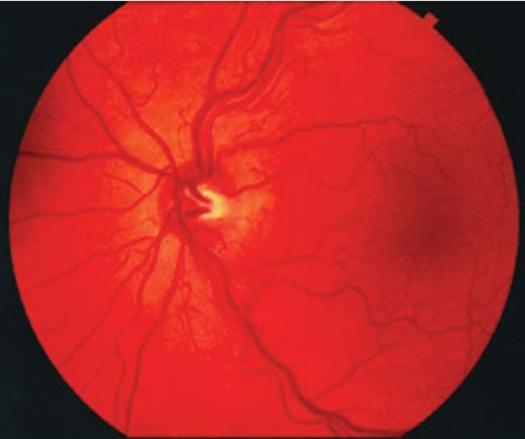

线粒体疾病是一组临床异质性疾病。它们可由核DNA或线粒体DNA(mtDNA)突变引起。有些仅影响单一器官,但许多涉及多个器官系统,且常表现出明显的神经和肌病特征。眼睛经常受到影响,肌肉和大脑也会受累,但多系统疾病很常见。眼部表现包括白内障、视网膜病变、视神经萎缩、皮质性视力丧失、上睑下垂和眼肌麻痹。卡恩斯-塞尔综合征(KSS)、线粒体脑肌病伴乳酸血症和卒中样发作(MELAS)、肌阵挛性癫痫伴破碎红纤维肌病(MERRF)以及莱伯遗传性视神经病变(LHON)是继发于mtDNA异常的知名临床病症,这些病症具有眼部表现。在进行性多系统疾病的鉴别诊断中应考虑线粒体功能障碍,特别是如果存在相关的神经眼科表现,这些表现可能是这些疾病的首发症状。

https://cdn.ncbi.nlm.nih.gov/pmc/blobs/202a/3038114/d7f442c55279/MEAJO-15-81-g002.jpg

https://cdn.ncbi.nlm.nih.gov/pmc/blobs/202a/3038114/20f99e4f5b9f/MEAJO-15-81-g001.jpg